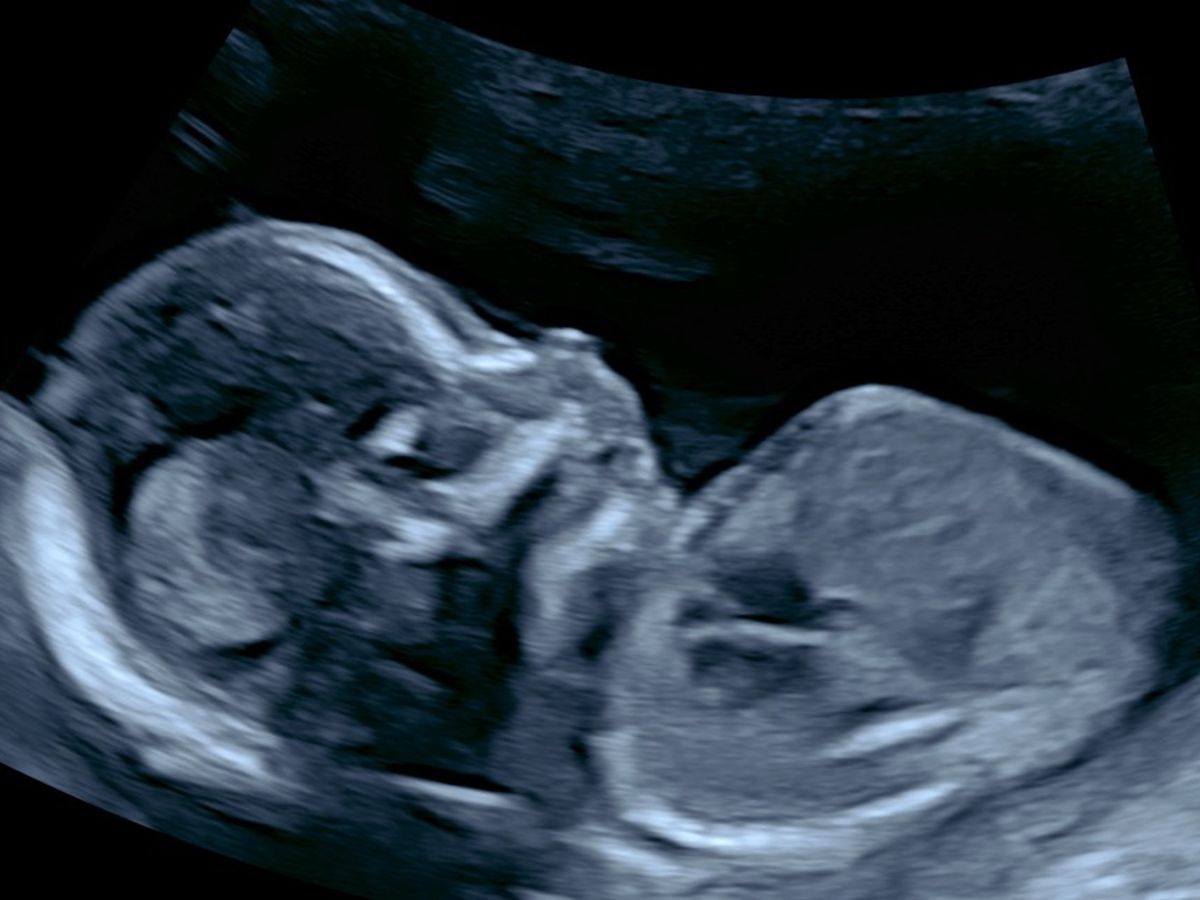

Our new baby Hector has been diagnosed with a heart condition called transposition of the great arteries as well as a heart abnormality which will require open heart surgery and other procedures to ensure his survival. While the odds are good for him the road is long, he will be required to have surgeries/procedures as soon as he is born and ongoing for months into his newborn life. Which will require lots of changes in our home, health and work schedules.